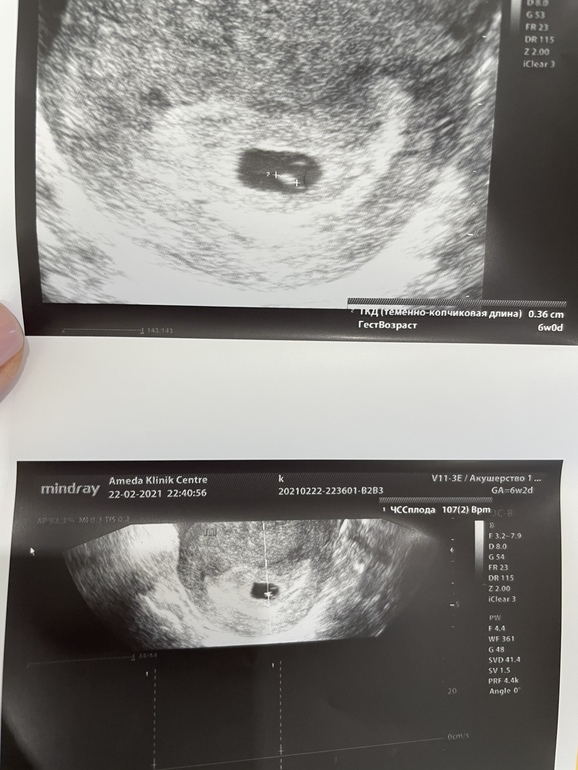

Узи 6 нед. 2 дн. и сердцебиение❤️

УЗИ, КТГ, доплерВсем добрый вечер 💐 Сходила сегодня на узи , всё в порядке , бусинка подросла , сердцебиение 107 ударов , ктр 3,6 , что соответствует 6 нед. беременности.